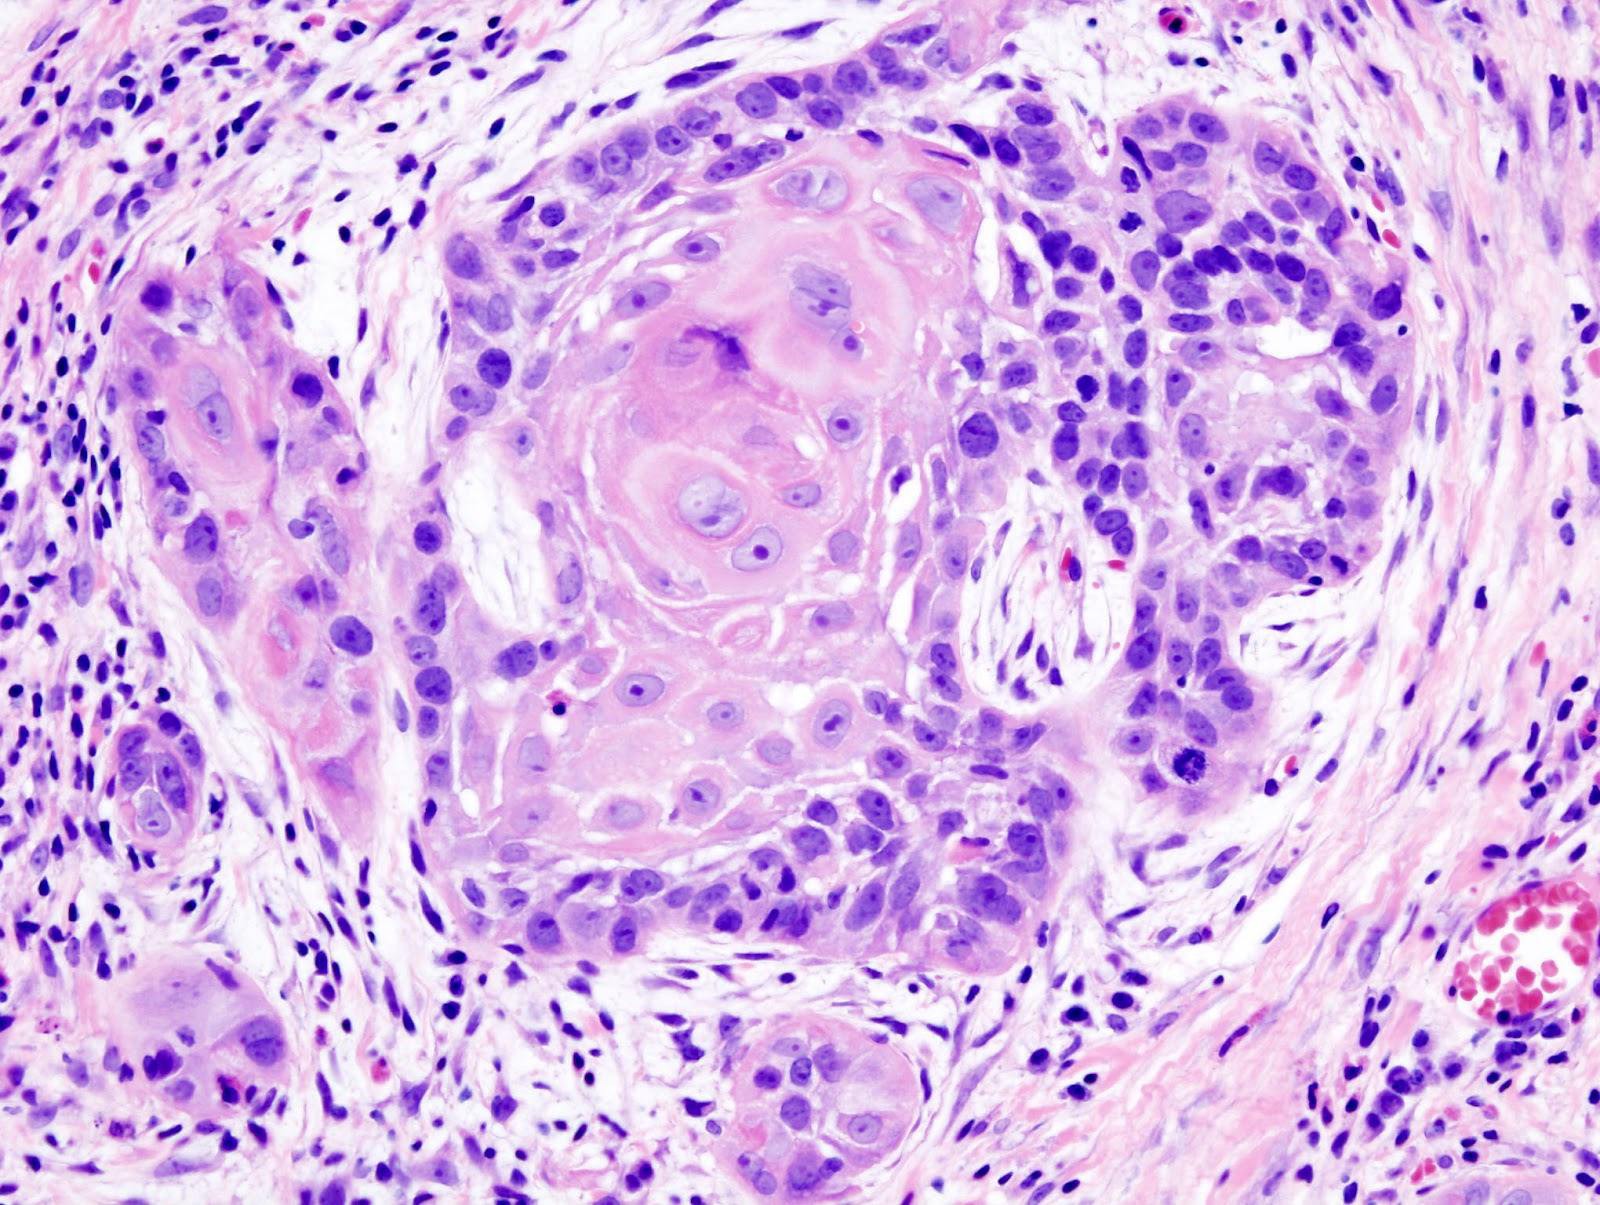

Bác sĩ Chu Kiến Anh nói: "Tôi xem phim chụp X quang phần ngực của cô gái, thoạt nhìn tôi thấy đó là giai đoạn cuối của ung thư phổi biểu mô tuyến, lập tức làm nội soi khí quản, cuối cùng đúng như tôi suy luận. Do ung thư phổi dễ bị phán đoán là viêm phổi, có ung thư phổi, khối u giống như súp lơ, nhìn có thể phân biệt ra, nhưng có ung thư phổi rất "xảo quyệt", hình ảnh và hình thái giống như viêm phổi, nó chỉ là một mảnh mờ".

Ung thư biểu mô tuyến phổi?

Ung thư biểu mô tuyến phổi thường bắt đầu ở các mô nằm gần các phần ngoài của phổi, và thường xuất hiện một thời gian dài trước khi gây ra các triệu chứng và được chẩn đoán. Ung thư biểu mô tuyến là loại ung thư phổi phổ biến nhất ở phụ nữ và thường gặp ở những người không hút thuốc.